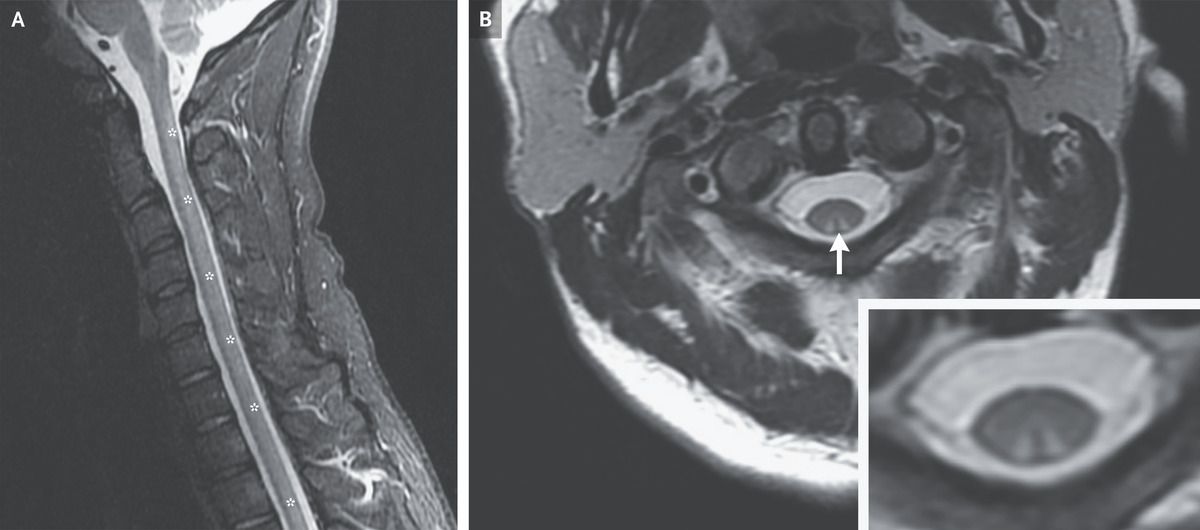

A 32-year-old man presented to the emergency department with a 6-week history of tingling in his arms and legs and a 2-week history of inability to walk. Two months before presentation, he had begun inhaling nitrous oxide — also known as “whippets” or “laughing gas” — daily. On physical examination, the Romberg test was positive, and sensory ataxia, impaired proprioception and vibratory sensation, and preserved nociception were noted. Magnetic resonance imaging of the whole spine showed hyperintensity in the posterior spinal cord from C1 to T12 on T2-weighted images (Panel A, asterisks). Axial images revealed a lesion in the dorsal column that was hyperintense on both T2-weighted images and fluid-attenuated inversion recovery (FLAIR) sequence, a finding known as the “inverted-V sign” that is seen in subacute combined degeneration (Panel B, arrow and inset). The patient’s vitamin B12 level was 107 pg per milliliter (reference value, >231). There was no macrocytic anemia. Antibody testing for autoimmune gastritis was negative. A diagnosis of subacute combined degeneration associated with nitrous oxide use was made. Long-term use of nitrous oxide causes the inactivation of vitamin B12, which then interrupts methionine synthase activity. After the patient ceased nitrous oxide use and received treatment with cyanocobalamin injections for 2 weeks, his vitamin B12 level normalized. At the 4-week follow-up, he was able to walk independently.